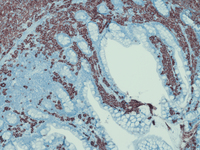

Biopsy immunostains

Immunostains with tryptase (top left), CD117 (top right) and CD25 (bottom left) can be used to highlight the mast cells and differentiate them from megakaryocytes. Note the atypical multinucleated mast cell in the center. CD25 stain shows a focal cluster of mast cells positive for CD25 while CD2 (bottom right)  is weakly positive in rare atypical mast cells while scattered T-/NK-cells are strongly positive for CD2.